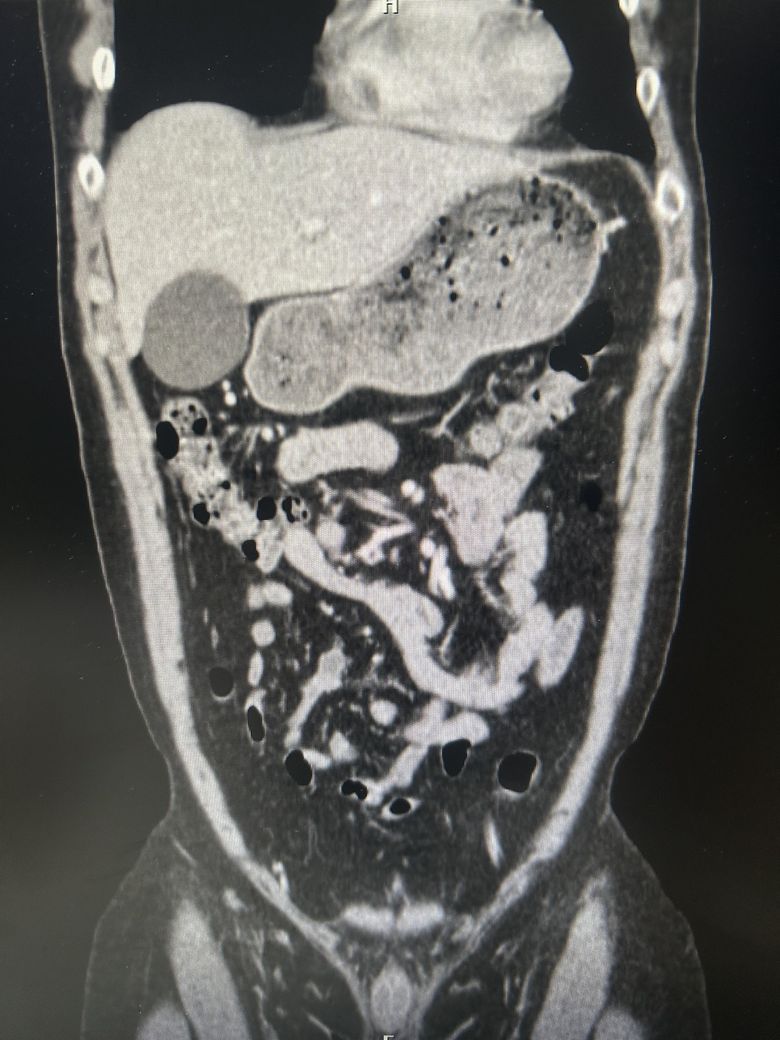

담낭염일 까요?? (CT 사진 있어요)

우상복부 통증(좌상복부 통증도 생김), 오른쪽 어깨에서 허리까지통증, 소화불량, 팽만감,답답함, 설사 증상이 있는데..... 담낭염이 맞을까요?

• 1번 째 사진

CT에서 담낭염은 담낭벽이 두꺼워보이고 벽이 조영증강되는데

환자분 자료의 경우 그런 소견이 뚜렷하게 보이지는 않는 것 같습니다.

• 애매합니다. 담낭의 크기가 다소 늘어나 보이긴 합니다만, 당남염을 강력하게 의심할만한 다른 소견들이 보이지는 않습니다. 가령 담낭의 벽이 두꺼워지거나 담낭 주변의 염증 소견, 담낭 목을 막고 있는 담석 등이 따로 관찰되거나 하지는 않기 때문에 담낭염을 강력하게 의심하기는 어려워 보입니다. 우상복부의 압통 및 머피징후 등의 신체검진 소견이 있다면 담낭염의 가능성을 고려해볼 수 있겠습니다만, 해당 CT 소견만으로는 판단하기 어렵습니다.

첨부해주신 CT 영상에는 담낭 주변에 두드러지는 염증소견이 관찰되지 않습니다. 다만 영상의 모든 단면을 확인한 것이 아니라서 담석증의 여부에 대해서는 확답드릴 수 없습니다. 증상이 지속되면 내과에서 진료를 받아보시는 것을 권해드립니다.